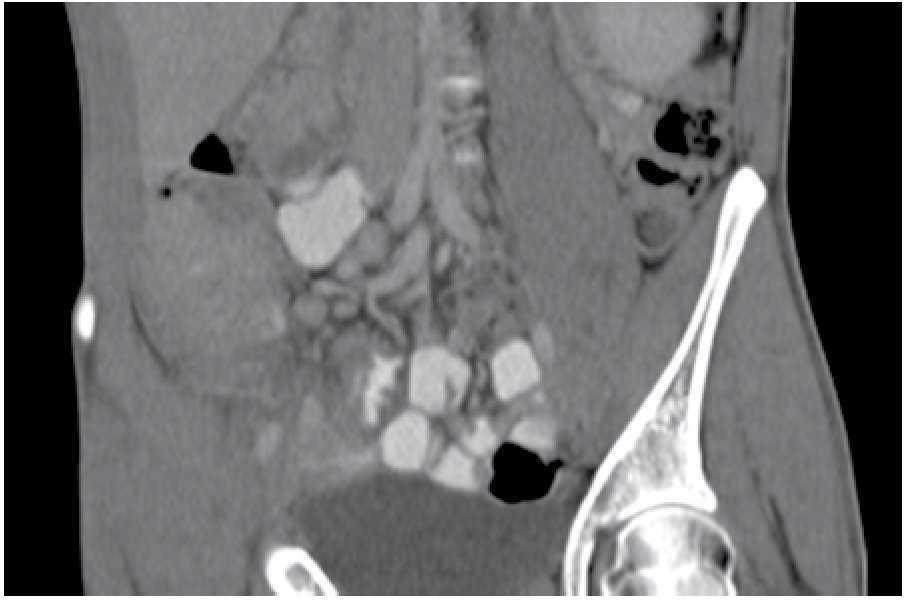

Paciente masculino de 28 años de edad, originario y residente de Chiapas, con un año de evolución, quien presentaba cuadros de estreñimiento y dolor abdominal ocasional, pérdida de peso de 7 Kg en seis meses, además de consumo de leche sin pasteurizar en dos ocasiones. Fue valorado por múltiples gastroenterólogos, se le realizaron estudios de endoscopia y colonoscopia, sin llegar a un diagnóstico preciso. Por nuevo cuadro de cuatro días de evacuaciones disminuidas en consistencia, 7/día, sin moco, ni sangre, con tenesmo y pujo tras la ingesta de cualquier alimento, dolor abdominal 9/10, asociado a náusea, sin vómito, con escalofríos y elevación térmica, acudió a Urgencias para valoración. En los estudios se evidenció hemoglobina de 12.3 g/dL, plaquetas 155 000 mm3 y VSG 35 mm/h. En TC se observó hepatoesplenomegalia, adenopatías y zonas de estenosis en íleon terminal (Figuras 1 y 2). Se realizó enteroscopia retrógrada de un solo balón, en donde se observaron úlceras lineales en íleon medio y terminal con engrosamiento de la mucosa y la válvula ileocecal con colon normal (Figura 3). La evaluación de patología mostró ileítis aguda ulcerada y crónica granulomatosa, asociada con micobacterias (Figuras 4, 5 y 6). El paciente se egresó del hospital para manejo ambulatorio con medicamentos antifímicos.

Figura 2. Adenopatías pericecales.